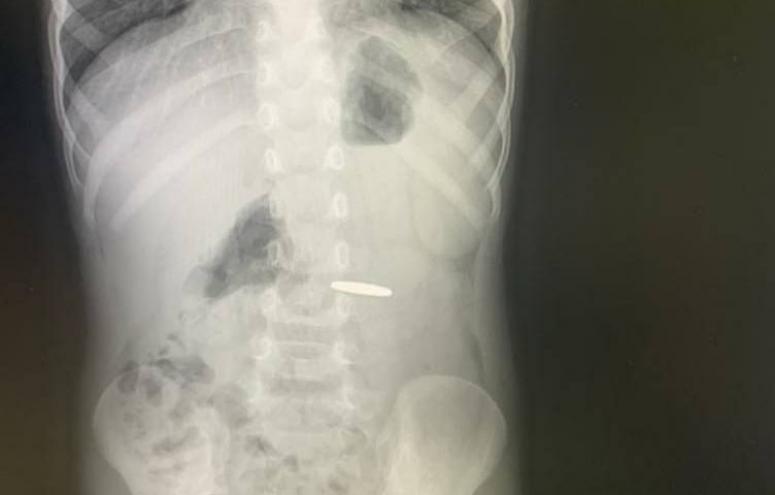

В Туапсе трехлетний ребенок проглотил монету

Инородный предмет пробыл в желудке малыша четыре дня

Врачи Туапсинской ЦРБ № 1 оказали неотложную помощь трехлетнему ребенку, проглотившему монету.

О произошедшем родители малыша узнали сразу же, но понадеялись, что монета выйдет естественным путем. Когда этого не произошло, пришлось обратиться за помощью к врачам.

Наличие монеты в желудке ребенка подтвердил рентгеновский снимок, который сделали в больнице. После сдачи необходимых анализов и консультаций педиатра и анестезиолога провели лечебную гастроскопию. Монету извлекли.